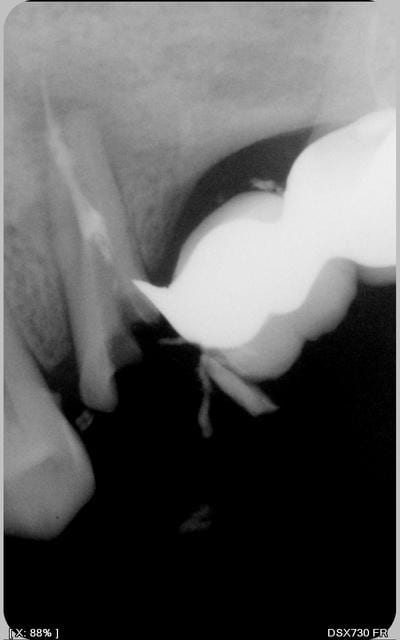

oh la jolie perf. et tu comptes vraiment garder cette dent ?

gloups! apparemment tu n'as pu trouver qu'un seul canal.

Pas de possibilité de trouver le deuxième? Pas de lumière canalaire visible à la radio en tout cas.

Bon, sincèrement, suis pessimiste, ton cône dépasse pas mal de l'apex apparemment ou est-ce un artefact de la radio?

ce n'est pas un artefact et a mon sens, il n'y a pas de perf

apex ouvert

un seul canal arrivé à etre traité

dépassement apparent de cöne

je ne conserverai pas surtout en repilier de bridge

et donc implants à envisager

Azerty, je suis très pessimiste!

Le tenon originel était déjà dévié en direction de la furcation.

Il semble que lors de la reprise tu as poursuivi dans cette direction jusqu'à effraction dans le furcation.

Vu le rôle de pilier qui devrait échoir à cette dent, l'ensemble d'opérations qui consisterait à:

- reprendre le traitement au delà de la fausse route

- combler celle-ci au MTA

- cureter la furcation

- reconstituer le moignon par collage

me paraît un peu gonflé et le pronostic pour le moins réservé.